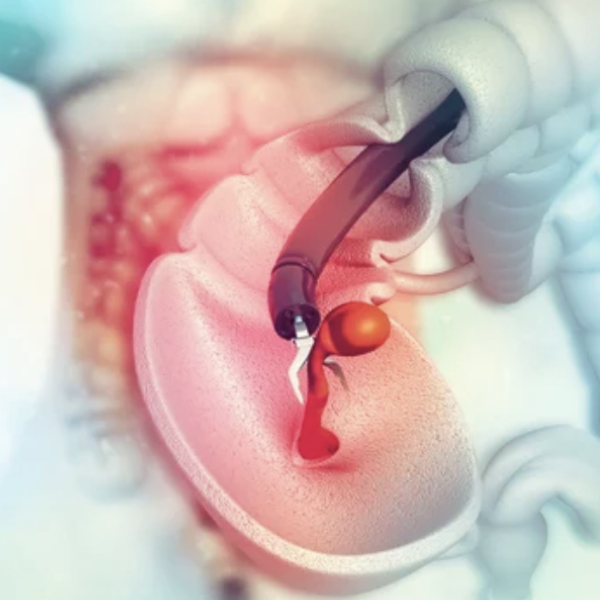

Extracción de hemorroides internas y externas causantes de sangrado rectal.